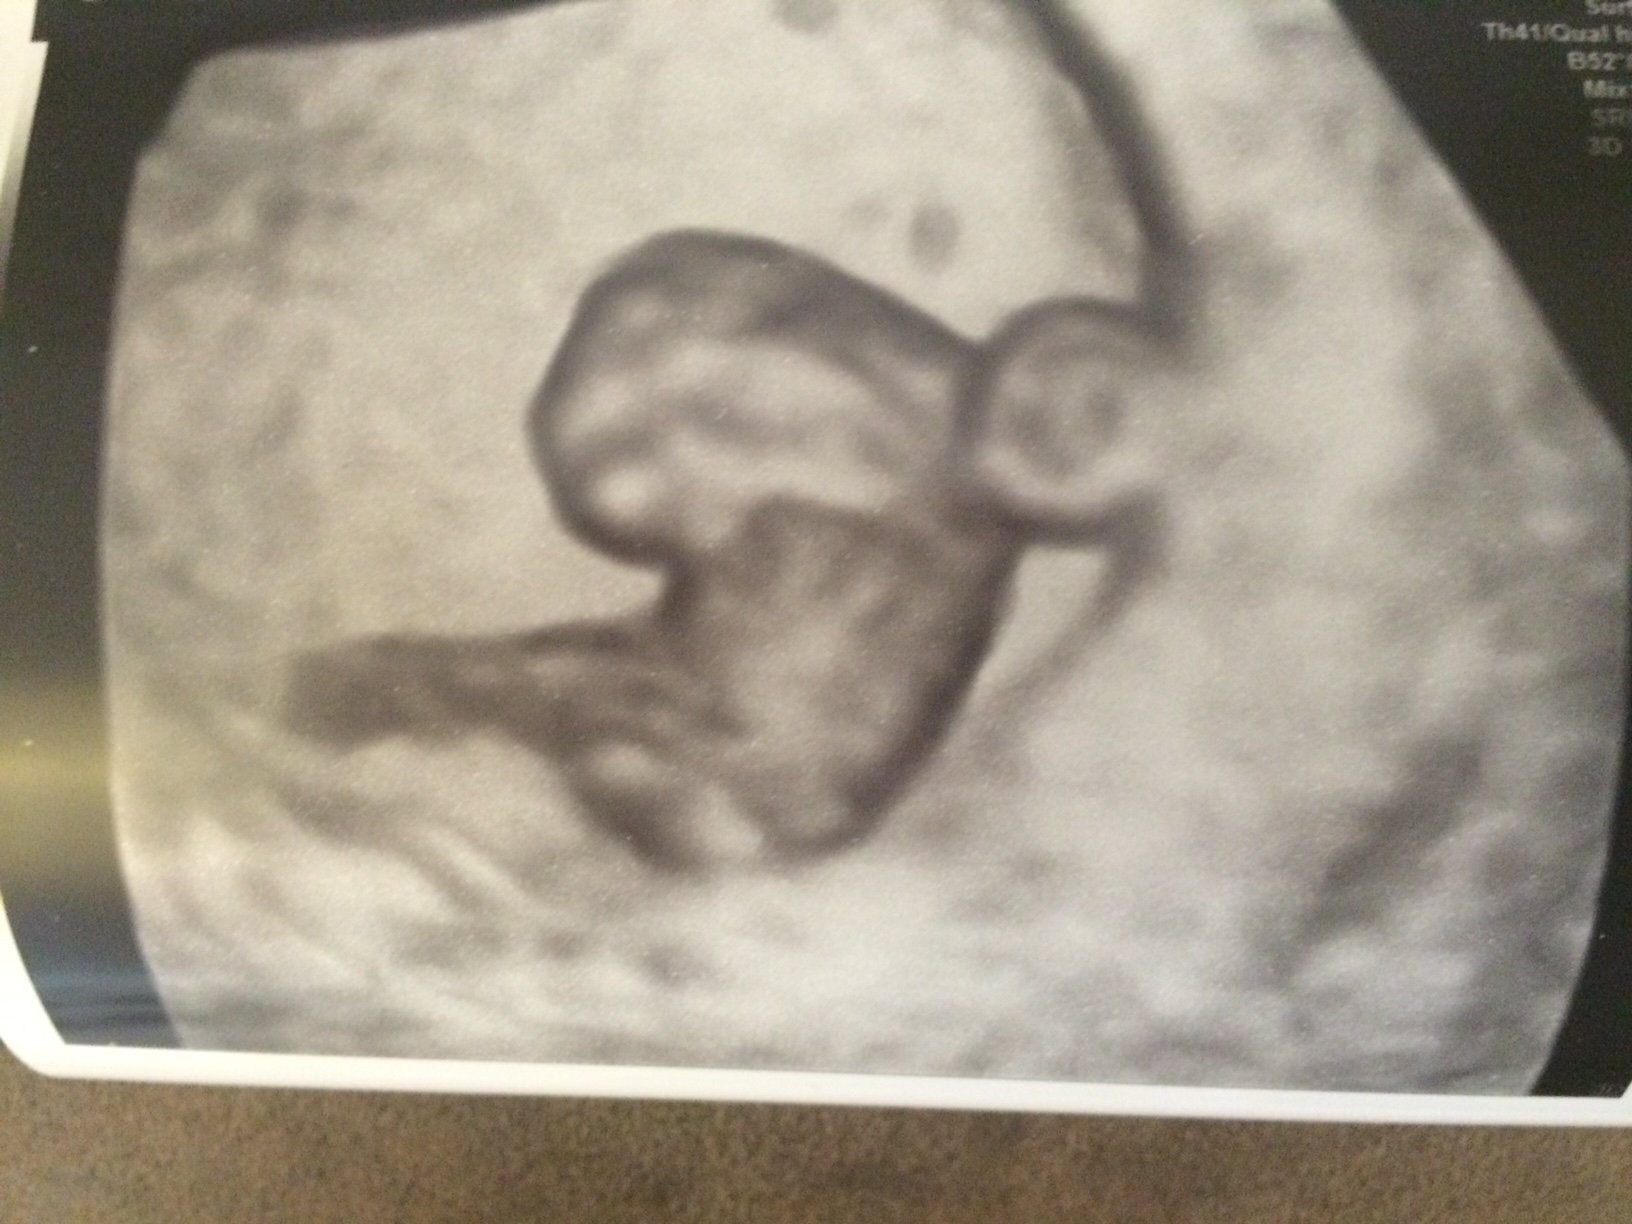

First ultrasound today! Kinda surprised because I was suppose to be 11 weeks according to my LMP but baby is measuring 8 weeks 3 days. But I am blessed to know baby is looking healthy with a HB of 169!